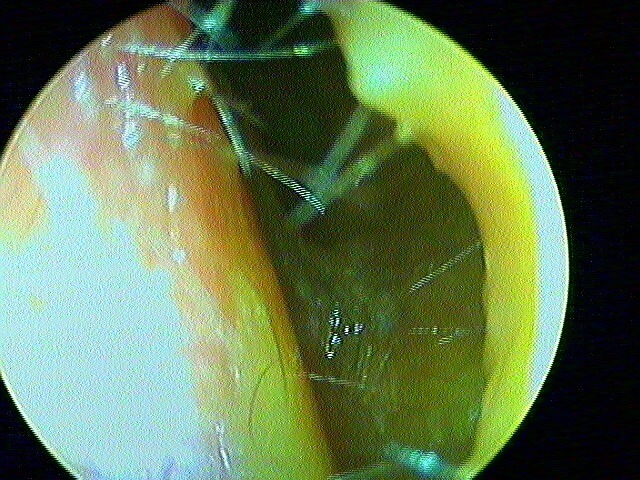

L' aspect de cavité d'évidement pétro-mastoidien sans récidive de cholestéatome, qui nécessitera une nettoyage annuel (la peau ne s'autonettoye plus, accumulation de cérumen):

Ici un phto-montage de 2 photos d'otoscopie: la cavité + CAE étaients trop larges: